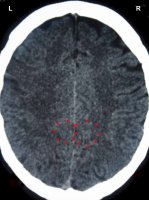

Tento sken mozku ukazuje Konstelaci postsenzorické kůry (viz diagram GNM) s Hamerovým ložiskem v relé periostu obou mozkových hemisfér. Dopad konfliktů narušuje synapse, které přenášejí elektrické signály (informace) z jednoho neuronu do druhého, což způsobuje zhoršení paměti.

Konvenční medicína předpokládá, že demence nějakým způsobem souvisí s "plaky" v mozku ("vědci přesně nevědí, jakou roli hrají plaky u Alzheimerovy choroby", Alzheimer's Association, www.alz.org). Ve skutečnosti jsou tyto "plaky" vápenaté usazeniny, které se časem tvoří v důsledku neustálých relapsů konfliktů, které přerušují léčebný proces; zde je to znázorněno na obou hemisférách (post)senzorické kůry, oblasti mozku, která biologicky odpovídá Konfliktům odloučení. Typickými Konflikty odloučení jsou smrt celoživotního partnera, ztráta partnera nebo přítele, malý nebo žádný kontakt s nejbližší rodinou (děti, vnoučata) nebo nutnost přestěhovat se do domova důchodců.